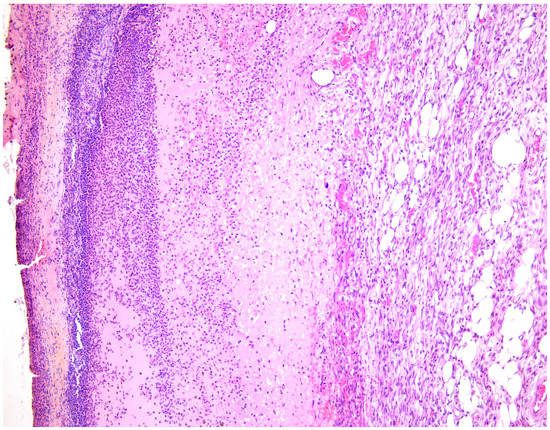

—fibrin clot,

—granulation tissue,

—adipose tissue.